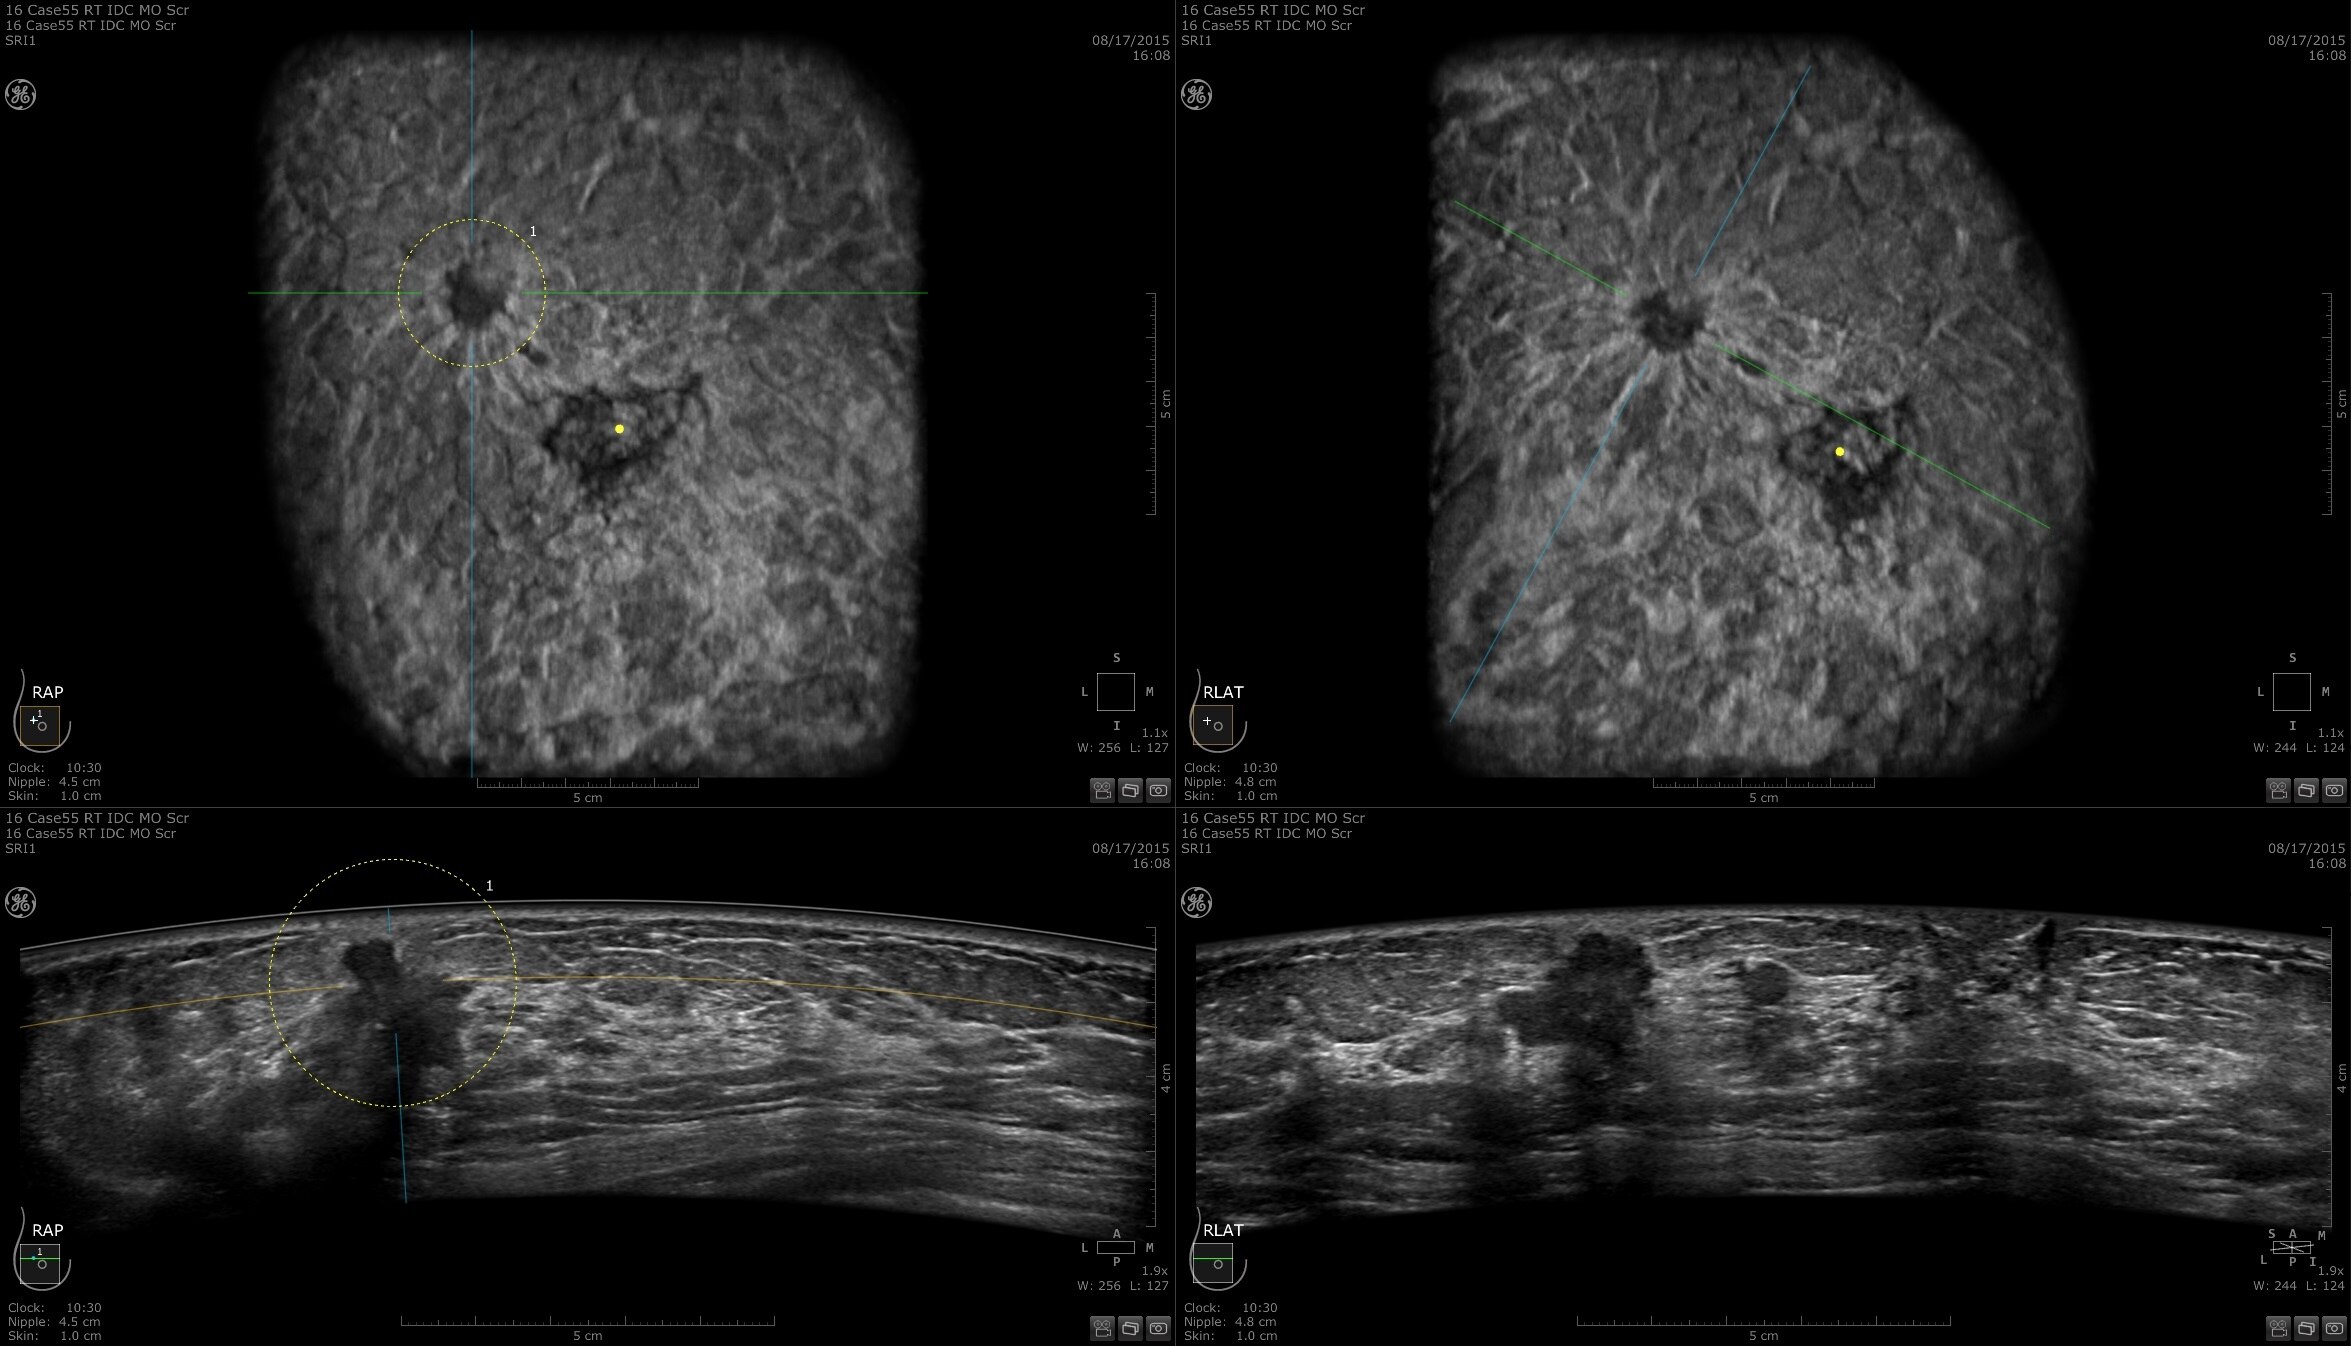

DIAGNOSIS & STAGING

Lesion characterization for confident staging in dense breasts

Invenia ABUS 2.0 uses the latest ultrasound innovations and AI based solutions to help improve precise diagnosis and elevate clinical confidence.